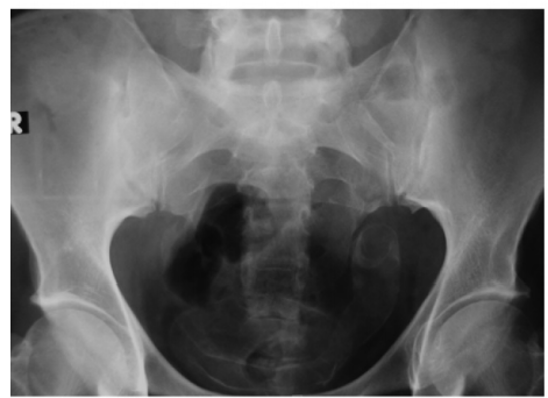

history of schistosomiasis

schistosomiasis